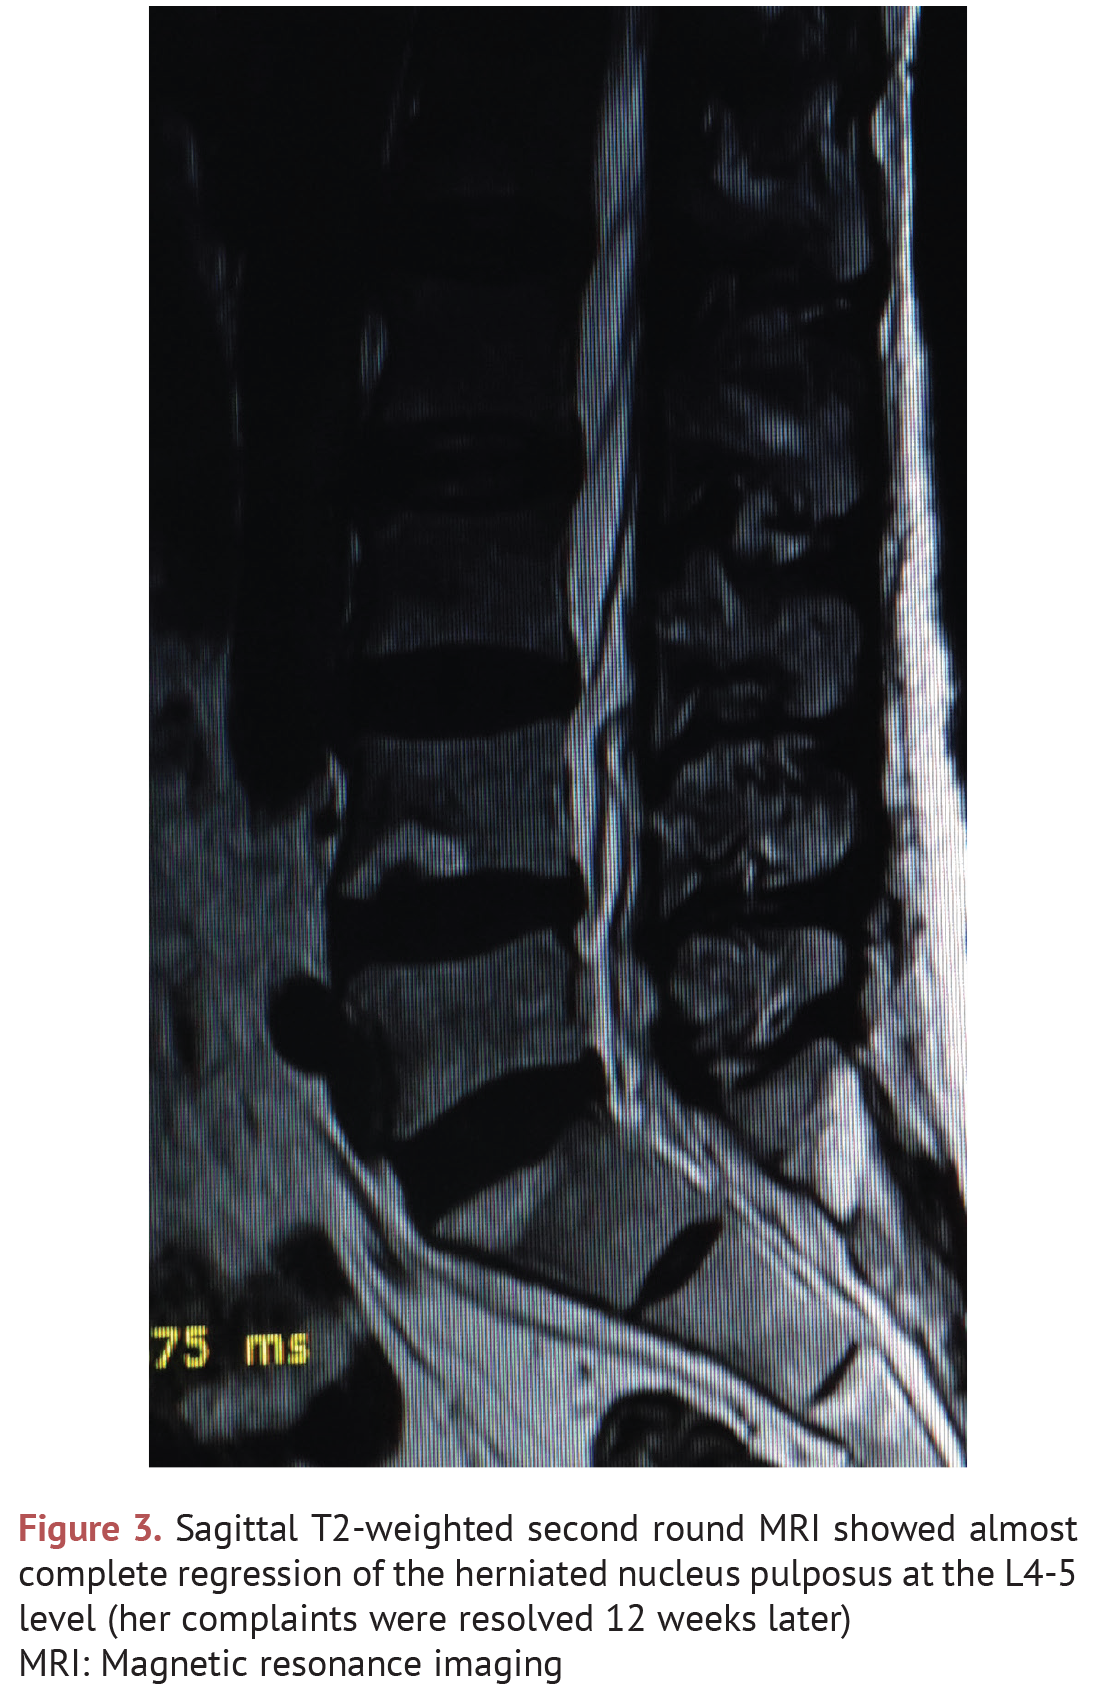

SPONTANEOUS REGRESSION OF LUMBAR DISC HERNIATIONS The Journal of

SPONTANEOUS REGRESSION OF LUMBAR DISC HERNIATIONS The Journal of Lumbar Herniation Journal Physical therapy is performed to alleviate symptoms and improve qol and pain or functional impairment in patients with lumbar. Lumbar disc herniations are common causes of lower back pain, neurological dysfunction, and buttock/leg pain. Disc herniations can manifest in lumbar radiculopathy, neurogenic claudication, and cauda equina syndrome based on the location and size of the herniation and other possible associated. Lumbar Herniation Journal.

SPONTANEOUS REGRESSION OF LUMBAR DISC HERNIATIONS The Journal of Lumbar Herniation Journal Lumbar disc herniations are common causes of lower back pain, neurological dysfunction, and buttock/leg pain. Substantial advancements have been made in the cause, diagnosis, imaging, and treatment options available for patients with. Lumbar disc herniation (ld) is more beneficial than conservative therapy (cc) in relieving back pain and leg pain, according to an. Disc herniations can manifest in lumbar radiculopathy,. Lumbar Herniation Journal.